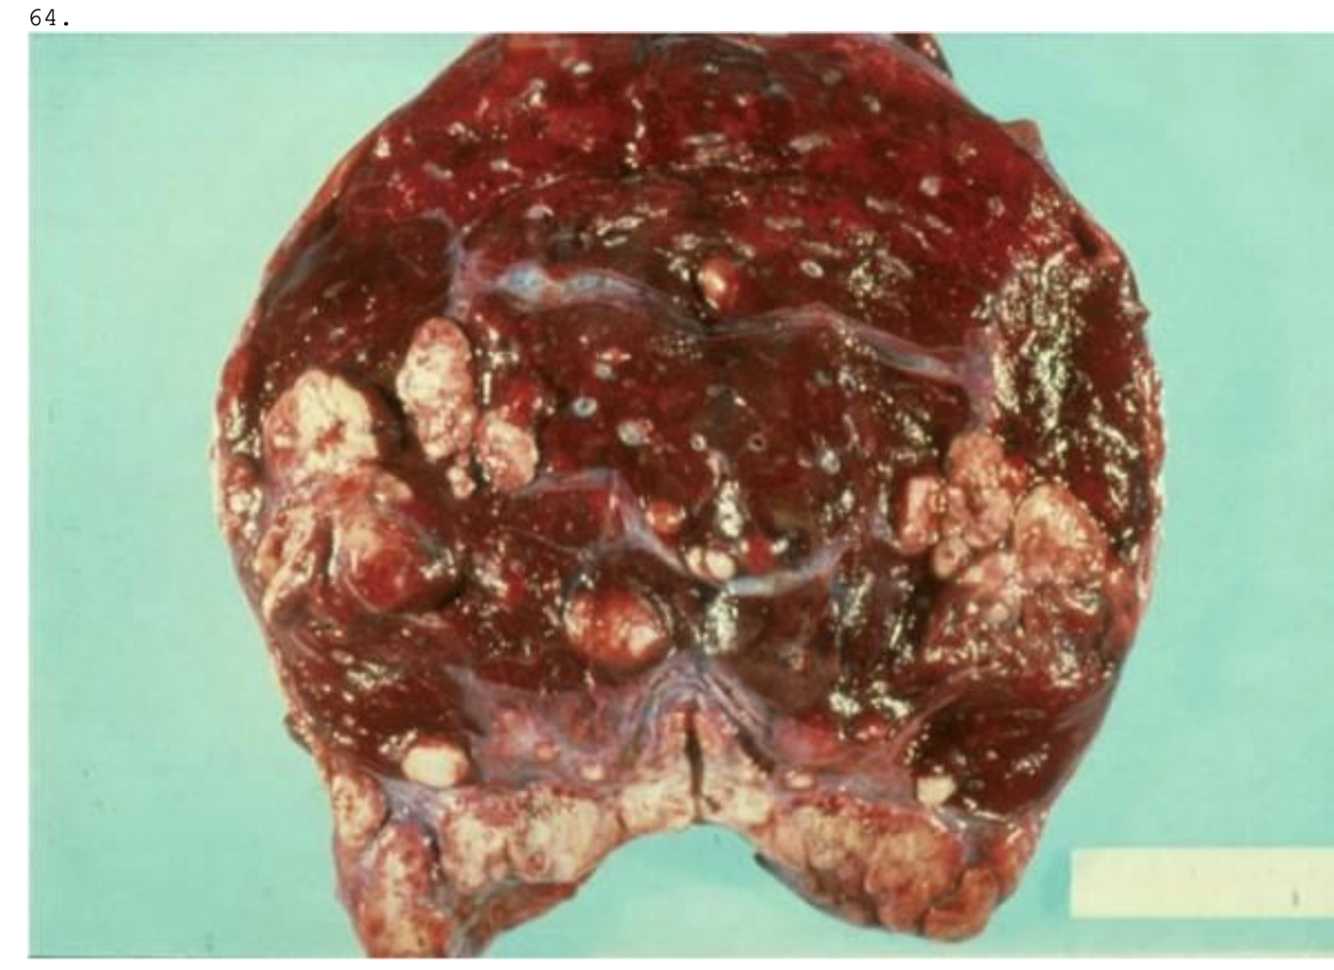

En 57-årig kvinde, som har røget og drukket siden ungdommen, dør kort efter indlæggelsen med symptomer på hjerneblødning. Ved obduktionen findes lungeforandringer som vist på billedet. Hvilken af nedennævnte diagnoser er mest sandsynlig?

a. Metastaser fra malignt astrocytom

b. Metastaser fra adenokarcinom i pancreas

c. Metastaser fra basocellulært karcinom

d. Metastaser fra malignt melanom

*b. Metastaser fra adenokarcinom i pancreas

Rygning er disponerende faktor for pancreaskræft (25% øget risiko) - sundhed.dk